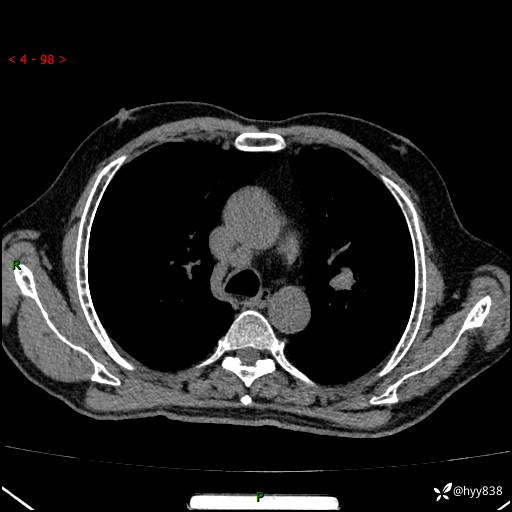

增强